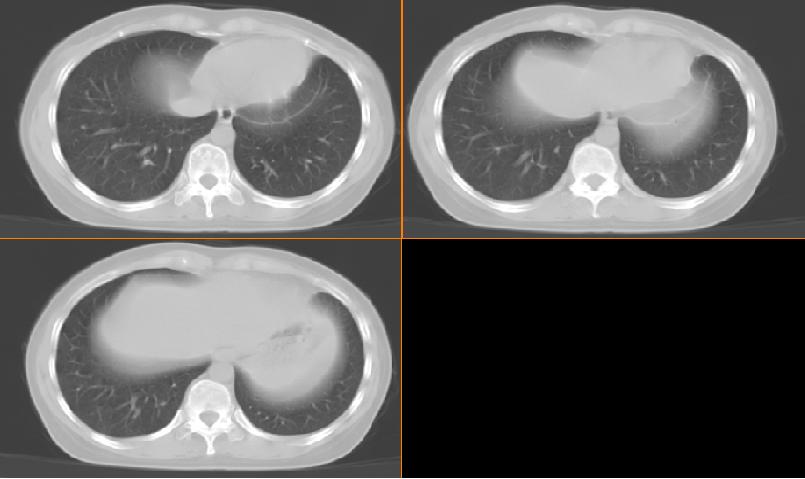

女,33岁,咳嗽5月。

左肺上叶前段致密,内见空气支气管征,相应部位胸膜增厚粘连,双肺上其他肺叶不同程度斑片状播散病灶,结合咳嗽5月的病史,考虑:双肺上叶继发性肺结核。

左肺上叶前段致密,内见空气支气管征,相应部位胸膜增厚粘连,双肺上其他肺叶不同程度斑片状播散病灶,结合咳嗽5月的病史,考虑:双肺上叶继发性肺结核伴左肺上叶肺含气不良。